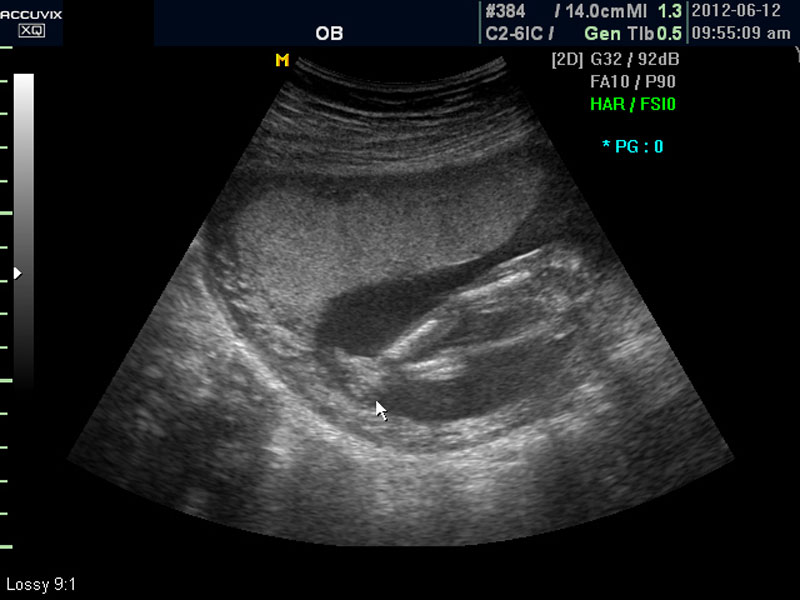

임신 중기의 초음파에서는 아기의 크기, 심장 박동이나 활동의 정도, 각종 장기의 구성이 정상인가 하는 것을 살펴 보게 됩니다.

태아의 대부분 장기는 임신 중기에는 이미 다 형성이 되고 이때부터는 크기가 커지면서 기능이 갖추어지는 시기입니다.

우선 초음파 사진에서 볼 것은 태아의 크기가 정상인가 하는 것입니다.

보통 태아의 발육은 머리부터 엉덩이까지의 크기인 CRL(Crown Rump Length의 약자)이 정상인가 하는 것과 태아의 두상 크기인 BPD(BiParietal Diameter의 약자)가 정상 범위에 들어 있는가 하는 것으로 판단합니다.

태아의 머리가 정상 모양인가 크기는 정상인가 하는 것을 살펴 본 후에는 태아의 크기를 측정하고 가슴, 복부, 엉덩이 부분, 상하지 부분이 정상인가 하는 것을 살펴 봅니다.

대신 첫번째 사진에서 보는 것처럼 태아의 전체 모습 특히 태아의 등쪽이나 복벽의 이상은 없는지 신경관 결손 등으로 인한 종괴가 있지는 않은지 관찰하며 태아의 복벽이나 등쪽은 일직선으로 매끈하게 보이는 것이 정상입니다.

첫번째 사진에서는 하지 부분은 대퇴부만 일부 보이며 이는 태아가 다리를 구부리고 있고 팔도 이리저리 움직여 머리 위나 목 쪽으로 두는 경우가 많아서 한번에 전체 모습을 찍기가 어려운 경우가 많습니다.